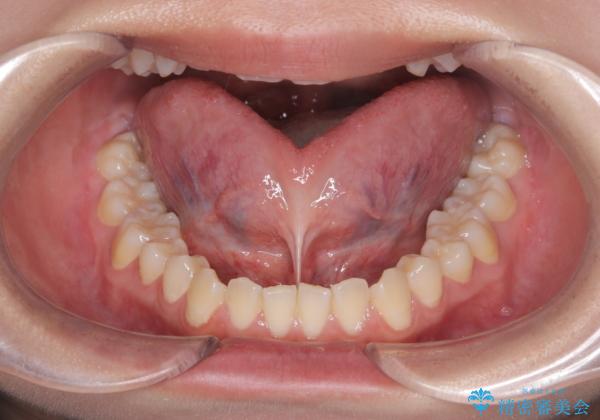

短い舌小帯に舌が引っ張られて舌がハート型になっています。

治療後、舌の可動域がかなり広がり患者様に大変ご満足していただけました。